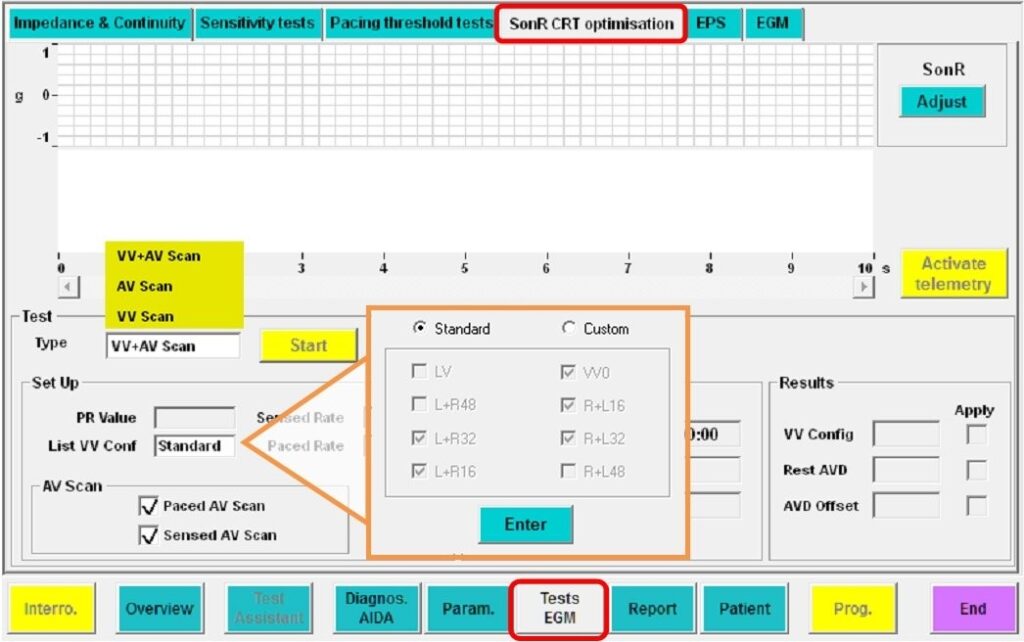

Tests d'optimisation des délais AV et VV

Test de l'optimisation des délais VV : Lundi à minuit :

Sept configurations BiV sont testées (de LV à RV 48 ms à RV à LV 48 ms ; par pas de 16 ms) en utilisant 6 retards AV différents, de 30 ms à la conduction spontanée moins 50 ms.

Ce test comprend 42 combinaisons et 252 mesures SonR.

Test d'optimisation du délai AV au repos : Lundi à 01:00h :

Après optimisation du délai VV, 11 délais AV différents, de 30 ms à la conduction spontanée moins 50 ms, sont testés. Ce test comprend 11 combinaisons et 66 mesures SonR.

Essai d'optimisation du délai de l'AV paced : Lundi à 02h00 :

Après optimisation du délai VV, 11 délais AV différents, de 30 ms à la conduction spontanée moins 50 ms, sont testés. Ce test comprend 11 combinaisons et 66 mesures SonR.

Test d'optimisation du délai AV pendant l'exercice : à partir du lundi à 12h00 :

L'optimisation du délai AV pendant l'exercice commence dès que la fréquence cardiaque a atteint une valeur programmée. Après l'optimisation du délai VV, 5 délais AV différents, de 30 ms à la conduction spontanée pendant l'exercice moins 50 ms, sont testés. Ce test comprend 5 combinaisons et 30 mesures SonR.

Test manuel

Des tests d'optimisation des délais AV/ VV peuvent également être réalisés au cours du suivi du patient, y compris avec la configuration LV only.